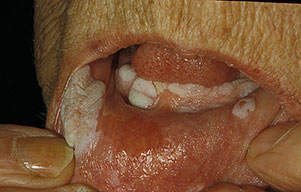

• Early lesions appear as white, translucent patches on an erythematous base. They may develop in previous areas of leukoplakia, lichen planus,8,9 chronic lupus erythematosus, cheilitis, candidiasis, or submucous fibrosis.

• The more fully developed lesions are white, soft, cauliflowerlike papillomas with a pebbly surface that may extend and coalesce over large areas of the oral mucosa.

• Ulceration, fistulation, and invasion locally into soft tissues and bone (eg, mandible) may occur. Oral verrucous carcinoma most commonly occurs on the buccal mucosa.7 Other sites of involvement are the alveolar ridge, upper and lower gingiva, floor of the mouth, tongue, tonsils, and vermilion border of the lip.